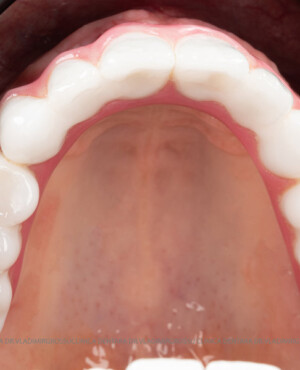

Metoda All-on-6 presupune inserarea chirurgicală a șase implanturi plasate strategic, pentru a asigura o proteză fixă stabilă și durabilă. Spre deosebire de conceptul All-on-4, recomandat în special pacienților cu deficit osos în zonele laterale ale maxilarului, All-on-6 are indicații mai largi și poate fi utilizat la majoritatea categoriilor de pacienți.

- Repartizarea uniformă a forțelor masticatorii asupra protezei;

- Posibilitatea realizării unei proteze cu 12-14 dinți, oferind un aspect estetic natural și funcționalitate optimă.